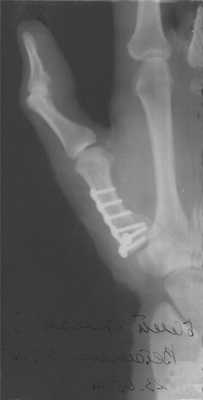

Рис. 36. Перелом крючковидной кости (указан стрелкой) при чрез- ладьевидно-чрескрючковидно-межпястно-латеролунарном вывихе кисти и энуклеации проксимального фрагмента ладьевидной кости с повреждением проксимальной запястной дуги у больного 37 лет в результате прямой травмы (рентгенограммы), а — в день травмы; б — через 10 нед после открытого вправления (предпринятого через месяц с момента травмы) с реплантацией фрагмента ладьевидной кости и костной пластики, с устранением расхождения поперечной запястной дуги и репозицией фрагмента крючковидной кости: отсутствие сращения крючковидной кости вследствие непроведения костной пластики и внутренней фиксации.

кровоснабжении, а от биомеханических причин. В связи с этим желательна первичная стабилизация фрагментов спицами или же — при наличии смещений — открытая репозиция и остеосинтез спицами с иммобилизацией в гипсовой повязке на срок 6—8 нед.